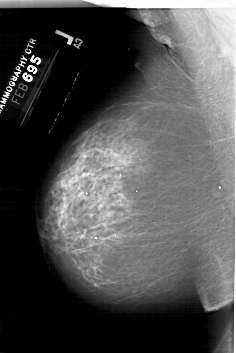

A_1999_1.LEFT_CC

LEFT_CC LINES 6751 PIXELS_PER_LINE 4006 BITS_PER_PIXEL 12 RESOLUTION 43.5 NON_OVERLAY